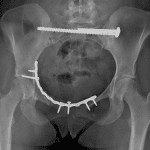

Age: 17

Sex: Female

Indication: MVC

Findings

- Superior left hemipelvic translation with diastasis of the pubic symphysis and left sacroiliac joint

- Acute fracture of the left sacral wing with a superiorly displaced S1 fragment

- Acute comminuted, mildly displaced fracture of the right superior pubic ramus

- Acute mildly displaced fracture of the right inferior pubic ramus

- Acute laterally distracted fracture of the left L5 transverse process

Diagnosis

- Unstable pelvic injury (vertical shear)

Unstable vertical shear pelvic injury with superior left hemipelvic translation and diastasis of the pubic symphysis and left sacroiliac joint.

Acute fractures of the left sacral wing with a superiorly displaced S1 fragment, right superior and inferior pubic rami, and of the left L5 transverse process with lateral distraction.

Hips are located.